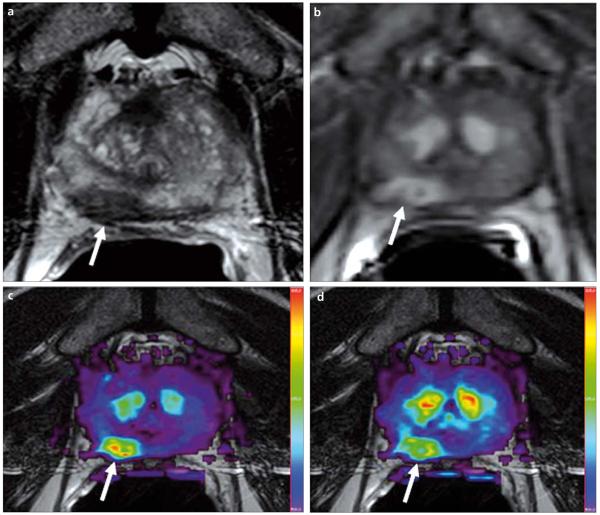

a–d. A 69-year-old male with prostate cancer. Axial T2W MR image demonstrates a low signal intensity focus at the right mid peripheral zone (arrow) (a). The lesion shows increased enhancement on axial T1W DCE-MR image (b); fusion of color-coded Ktrans (c) and Kep (d) maps delineate the tumor lesion (arrows).